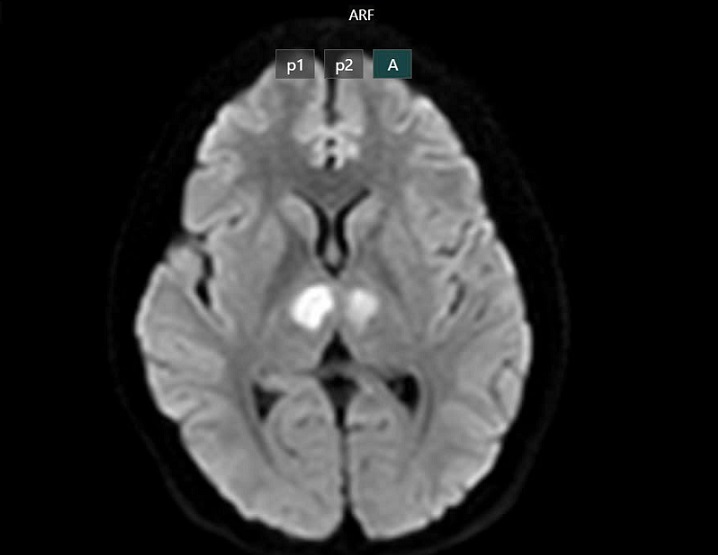

Cụ thể, khoảng 16h ngày 21/2 bệnh nhân vẫn nói chuyện với con, nhưng đến khoảng 19h30, gia đình phát hiện bệnh nhân trong trạng thái bất tỉnh, gọi hỏi không đáp ứng. Bệnh nhân không sốt, không co giật, không nôn. Người nhà đưa bệnh nhân đến bệnh viện tư để cấp cứu. Kết quả chụp MRI cho thấy não bệnh nhân có hình ảnh tổn thương vùng đồi thị hai bên. Gia đình xin chuyển bệnh nhân sang Bệnh viện Bạch Mai để được tiếp tục điều trị.

Phim chụp cho thấy não bệnh nhân bị tổn thương vùng đồi thị hai bên